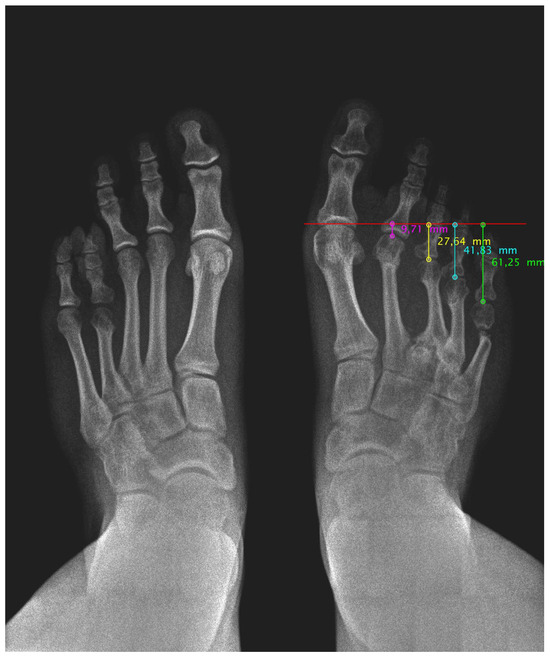

Finally, the radiological study confirmed a diaphyseal shortening of the third and fourth radius of the right foot (Figure 1). Her left foot also showed diaphyseal shortening of only the fourth radius with no symptoms.

Figure 1. Pre-surgical radiological image of both feet under load.